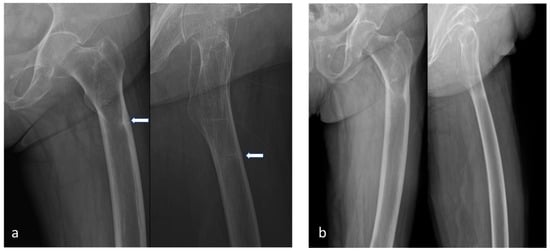

2. Case Presentation